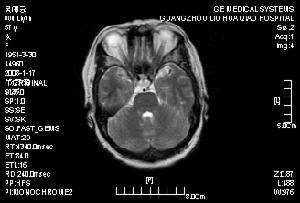

1.X線胸片可見肺門有蝴蝶形態片狀陰影並向周圍擴展的肺水腫徵象,心界擴大,心尖搏動減弱等。

2.心電圖竇性心動過速或各種心律失常,心肌損害,左房、左室肥大等。